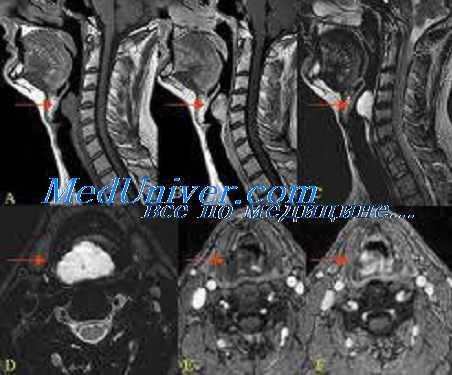

Мультифакториальная дисфагия у пациента со злокачественной опухолью головы и шеи. Изображения FEES пациента, которому проводилась лучевая терапия по поводу опухоли корня языка.

У пациента нарушена чувствительность гортани, при глотании гортань не смещается вверх.

(а) Голосовые складки подвижны.

(б) С помощью разбавленного яблочного сока удалось обнаружить скопление болюса в валлекулах. Имеются признаки «немой» аспирации (стрелка).

(в) Болюс (печенье) попадает в гортань.

(г) После того, как пациенту были даны инструкции, он смог свести голосовые складки, наклонил подбородок и совершил несколько форсированных глотков. Пищевой комок продвинулся без аспирации.